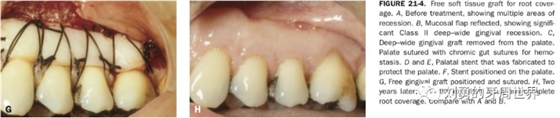

對于需要進行根面覆蓋的手術,移植瓣需要縫合固定到CEJ冠向1mm左右的位置。如下圖:

原因是:附著齦增寬的手術,受區(qū)骨膜面積大,血供好,因此用偏薄的就可以,而對于根面覆蓋的手術,受區(qū)外露根面沒有骨膜,血供差,因此取厚一點的,容易成活,對于牙槽嵴缺損的,建議取厚的,不是為了血供,而是為了更明顯的修復牙槽嵴的缺損。如下圖:

上面是附著齦增寬,因此取的薄一些。

上圖B23頰側牙槽嵴水平向塌陷明顯,為了增寬,取厚一點的齦瓣效果更好。